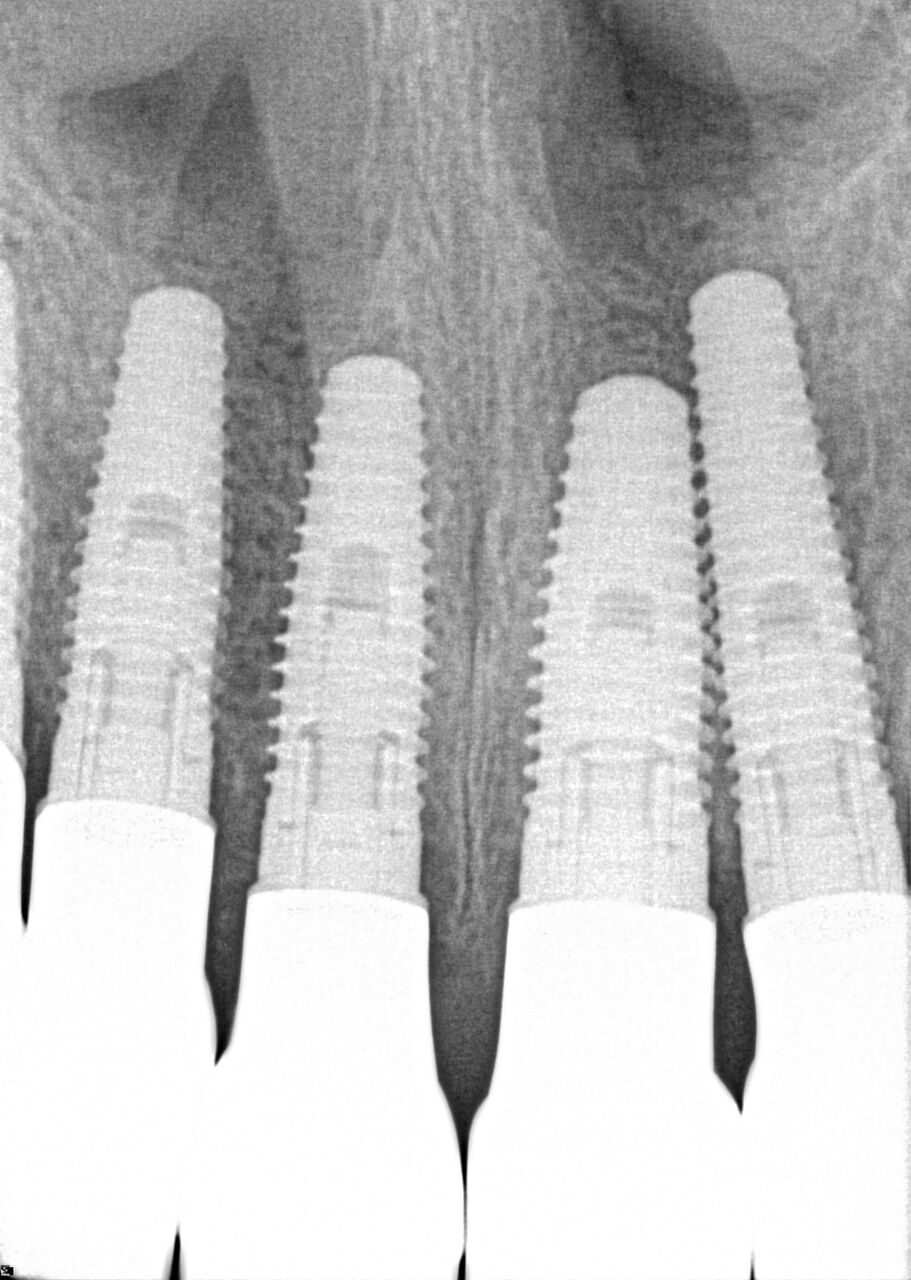

A 42-year-old man presented with a very loose bridge on Nos. 6 through 9 with periodontally compromised retainers on Nos. 6 and 9 (Figure 17 through Figure 19), and endodontically involved No. 10 with a calcified canal. Teeth Nos. 6, 9, and 10 were extracted, the sockets fully debrided, and pontic soft tissue on Nos. 7 and 8 sculpted to be symmetrical in soft tissue contour with the contralateral lateral incisor and central incisor locations. Implants were secured in position Nos. 6 through 10 (Figure 20) in excess of 45 Ncm, the bone was milled to provide unimpeded seating of temporary abutments, and temporary crowns were fabricated chairside and adjusted to be out of occlusion in centric relation and all excursions. The temporary crowns were cemented after extrusion of excess cement extraorally and the patient was prescribed antibiotics, analgesics, and instructed in postoperative care particular to immediately provisionally restored implants. At 6 months, integration was confirmed (Figure 20 through Figure 23) and after placement of scanning abutments, the implants and soft tissues were scanned. Final crowns were fabricated from the scanned images and were cemented after extrusion of excess cement extraorally (Figure 24 through Figure 26), and oral hygiene procedures were reviewed.

(20.) 6-month integration confirmation of Nos. 6 through 10.

Figure 20

(21.) 6-month integration confirmation of Nos. 6 through 10.

Figure 21

(24.) Radiograph of postoperative individual crowns on Nos. 6 through 10.

Figure 24

(25.) Radiograph of postoperative individual crowns on Nos. 6 through 10.

Figure 25